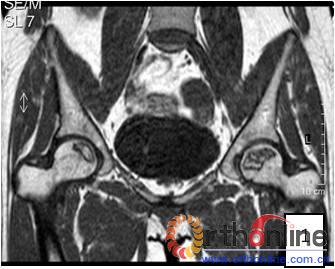

2.2 影像学结果 影像学结果与临床结果基本同步。临床结果优的36髋,34髋维持圆形且修复较完全(图1)。1例双髋Ⅲa激素性(SARS患者)ONFH,术后随访7年8月,X线片显示股骨头虽不圆,但临床HHS评分90分为优(图2)。功能为良的12髋,7髋股骨头不圆,但股骨头与髋臼匹配好,其余5髋股骨头维持圆形。临床评定为差的17髋,股骨头均有超过4mm塌陷,股骨头与髋臼匹配不好,股骨头内无折断,MRI未显示骨髓水肿,关节间隙呈不对称改变,CT扫描示软骨下骨折,MRI显示骨髓水肿。

图1 女,22岁,(1)双侧股骨头坏死右侧B型,左侧C1型;(2)打压植骨术(加入BMP2)后5年,CT显示植骨生长良好,关节功能正常(Harris评分96分);(3)术后7年关节功能维持正常,股骨头维持正常外形